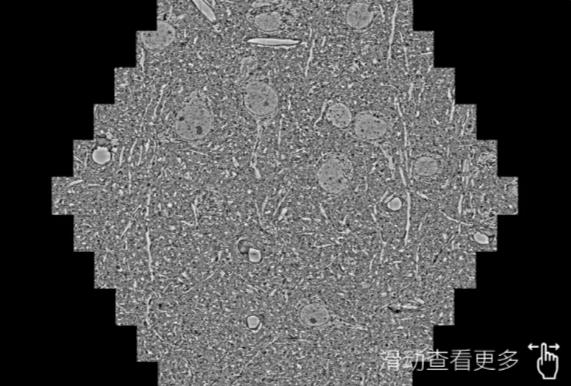

鼠脑切片。左图使用南岸蔡司南岸扫描电镜MultiSEM706对165μmx143pm面积区域成像,耗时仅需1.5秒。右图为鼠脑切片中30μm区域放大效果。样品由芝加哥大学B.Kasthuri提供。

使用蔡司高速南岸扫描电镜MultiSEM对1mm²人脑皮层组织进行高分辨成像,并对其中的各种细胞结构进行三维重构分析。左图展示了2x3mm²组织平面中锥体神经元的三维重构效果。右图显示了局部体积神经元三维重构。图像由哈佛大学chtman实验室提供,渲染图由D. Berger 制作。